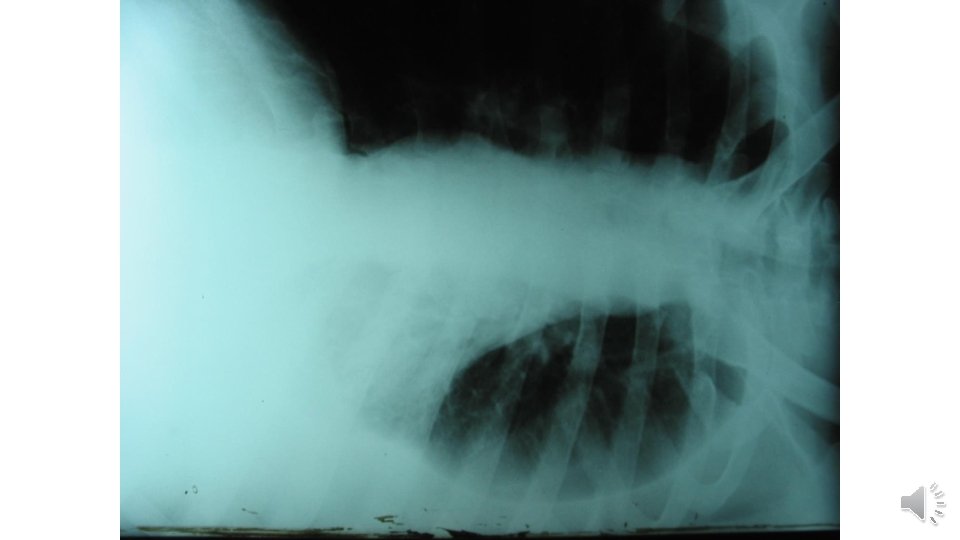

ﻣﻌﺎیﻨﻪ • • BP: 110/80 PR: 130 OT: 39. 8 RR: 22 Bi temporal Wasting No murmur Decreased left lung sound & dullness No hepatomegaly Splenomegaly O 2 sat: 79%

آﺰﻣﺎیﺸﺎﺕ • • WBC: 1700 P(71%) L(23%) M(3%) Hb: 8. 4 Plt: 158000 LFT: Normal ESR: 60 CRP: neg RF: neg

Pleural Fluid • • • PH: 7. 2 WBC: 1400 P(2%) M(97%) E(1%) RBC: 3400 Sugar: 32 Pr: 3. 5 / 5 LDH: 2500 • Smear & culture: neg